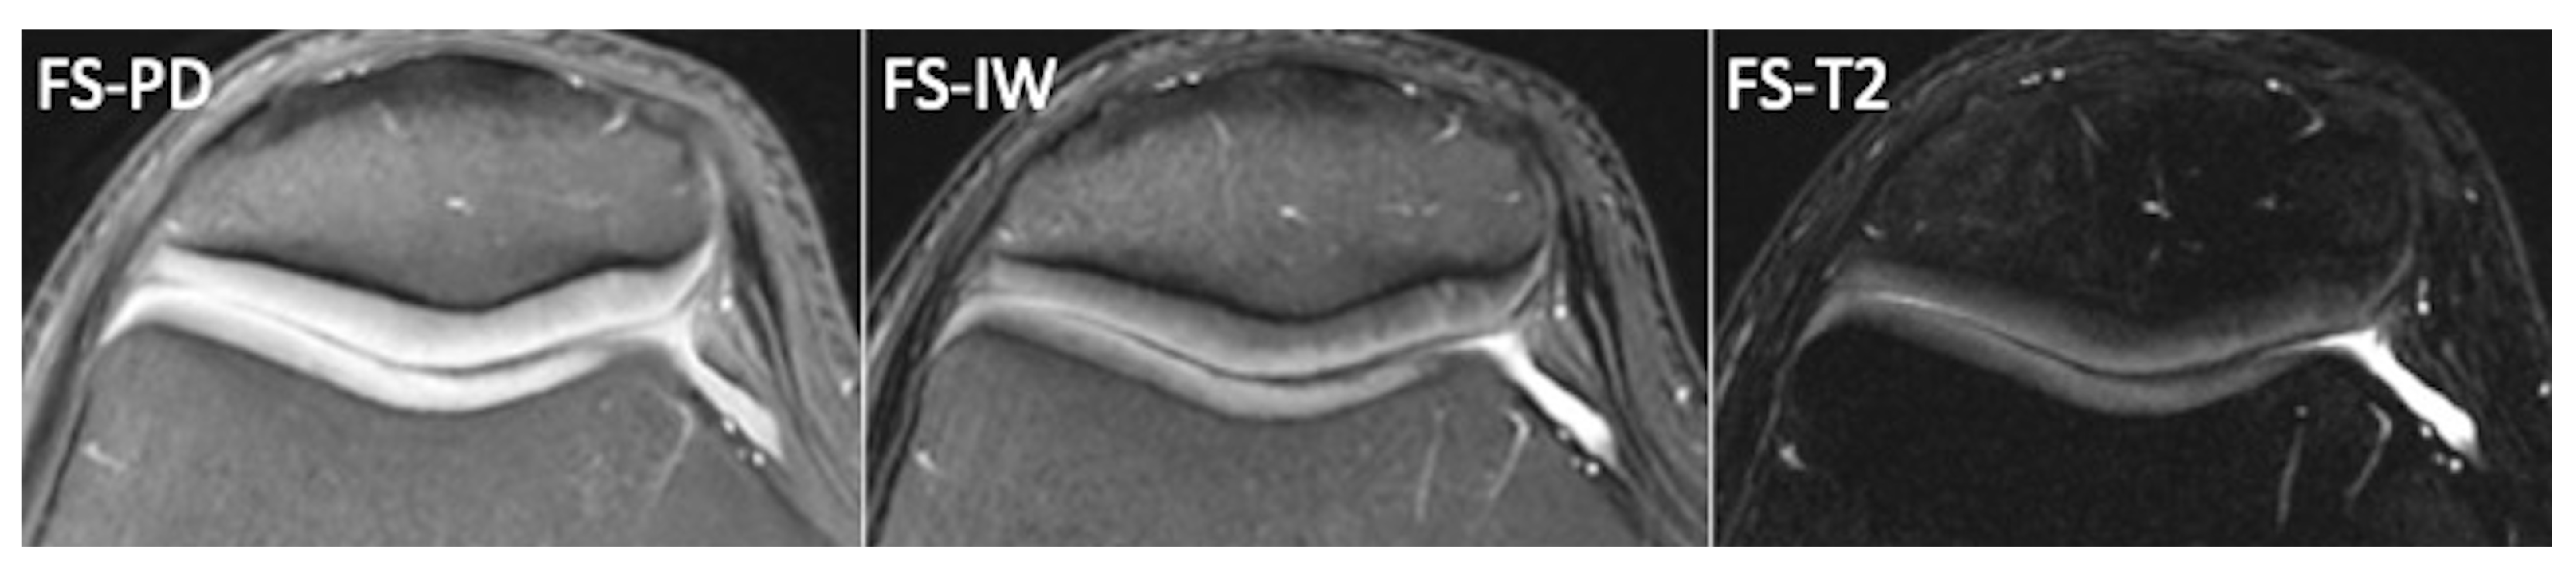

2.1. Conventional MRI

- Omoumi, P.; Mourad, C.; Ledoux, J.-B.; Hilbert, T. Morphological assessment of cartilage and osteoarthritis in clinical practice and research: Intermediate-weighted fat-suppressed sequences and beyond. Skelet. Radiol. 2023, 52, 2185–2198. [Google Scholar] [CrossRef]